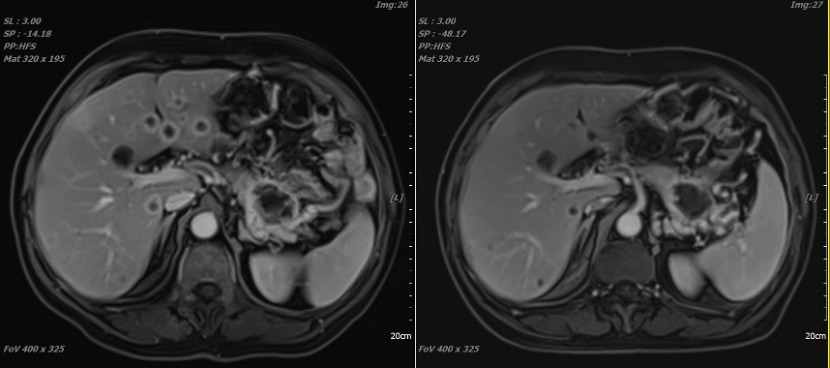

Medical History: The patient was admitted to the hospital in February 2024 due to abdominal pain without apparent provocation. A local abdominal CT scan revealed: A mass in the tail of the pancreas with malignant features, encasing the left renal vein and appearing to invade the left renal artery, stomach, and left adrenal gland. Several slightly hypodense nodules in the liver, suggest metastatic tumors. For further treatment, the patient visited our hospital on April 18, 2024. After admission, relevant examinations were completed. A pancreatic tumor biopsy indicated moderately differentiated pancreatic ductal adenocarcinoma. Immunohistochemical results showed: C-erbB-2 (0), CK19 (+), CK20 (-), CK7 (+), Ki-67 (index ≈ 5%), P53 (wild type), S100p (-). Gene testing detected a KRAS G12D mutation. An abdominal MRI scan suggested a mass in the tail of the pancreas, with local encasement of the left renal vein and unclear boundaries with the left adrenal gland, gastric wall, and left renal arteries and veins, most likely representing pancreatic cancer; multiple liver metastases were also observed. After excluding contraindications, the patient underwent carbon ion radiotherapy for pancreatic cancer and liver metastasis starting on May 1, 2024. The total dose for the pancreatic lesion was PTV 36Gy(RBE)/9Fx and PTVboost 22.5Gy(RBE)/5Fx; the dose for liver metastasis was PTV 40Gy(RBE)/10Fx and PTVboost 20Gy(RBE)/5Fx. Concurrently, the patient received chemotherapy with "gemcitabine + albumin-bound paclitaxel" on May 1 and May 8, 2024. A follow-up abdominal MRI scan after treatment indicated a decrease in the size of the lesion in the tail of the pancreas compared to the scan on May 13, 2024. Multiple liver metastases had also decreased in size for the most part.

Treatment Effect: After treatment, a follow-up abdominal MRI scan showed a decrease in the size of the pancreatic lesion and most liver metastases compared to previous scans.

Before treatment After treatment